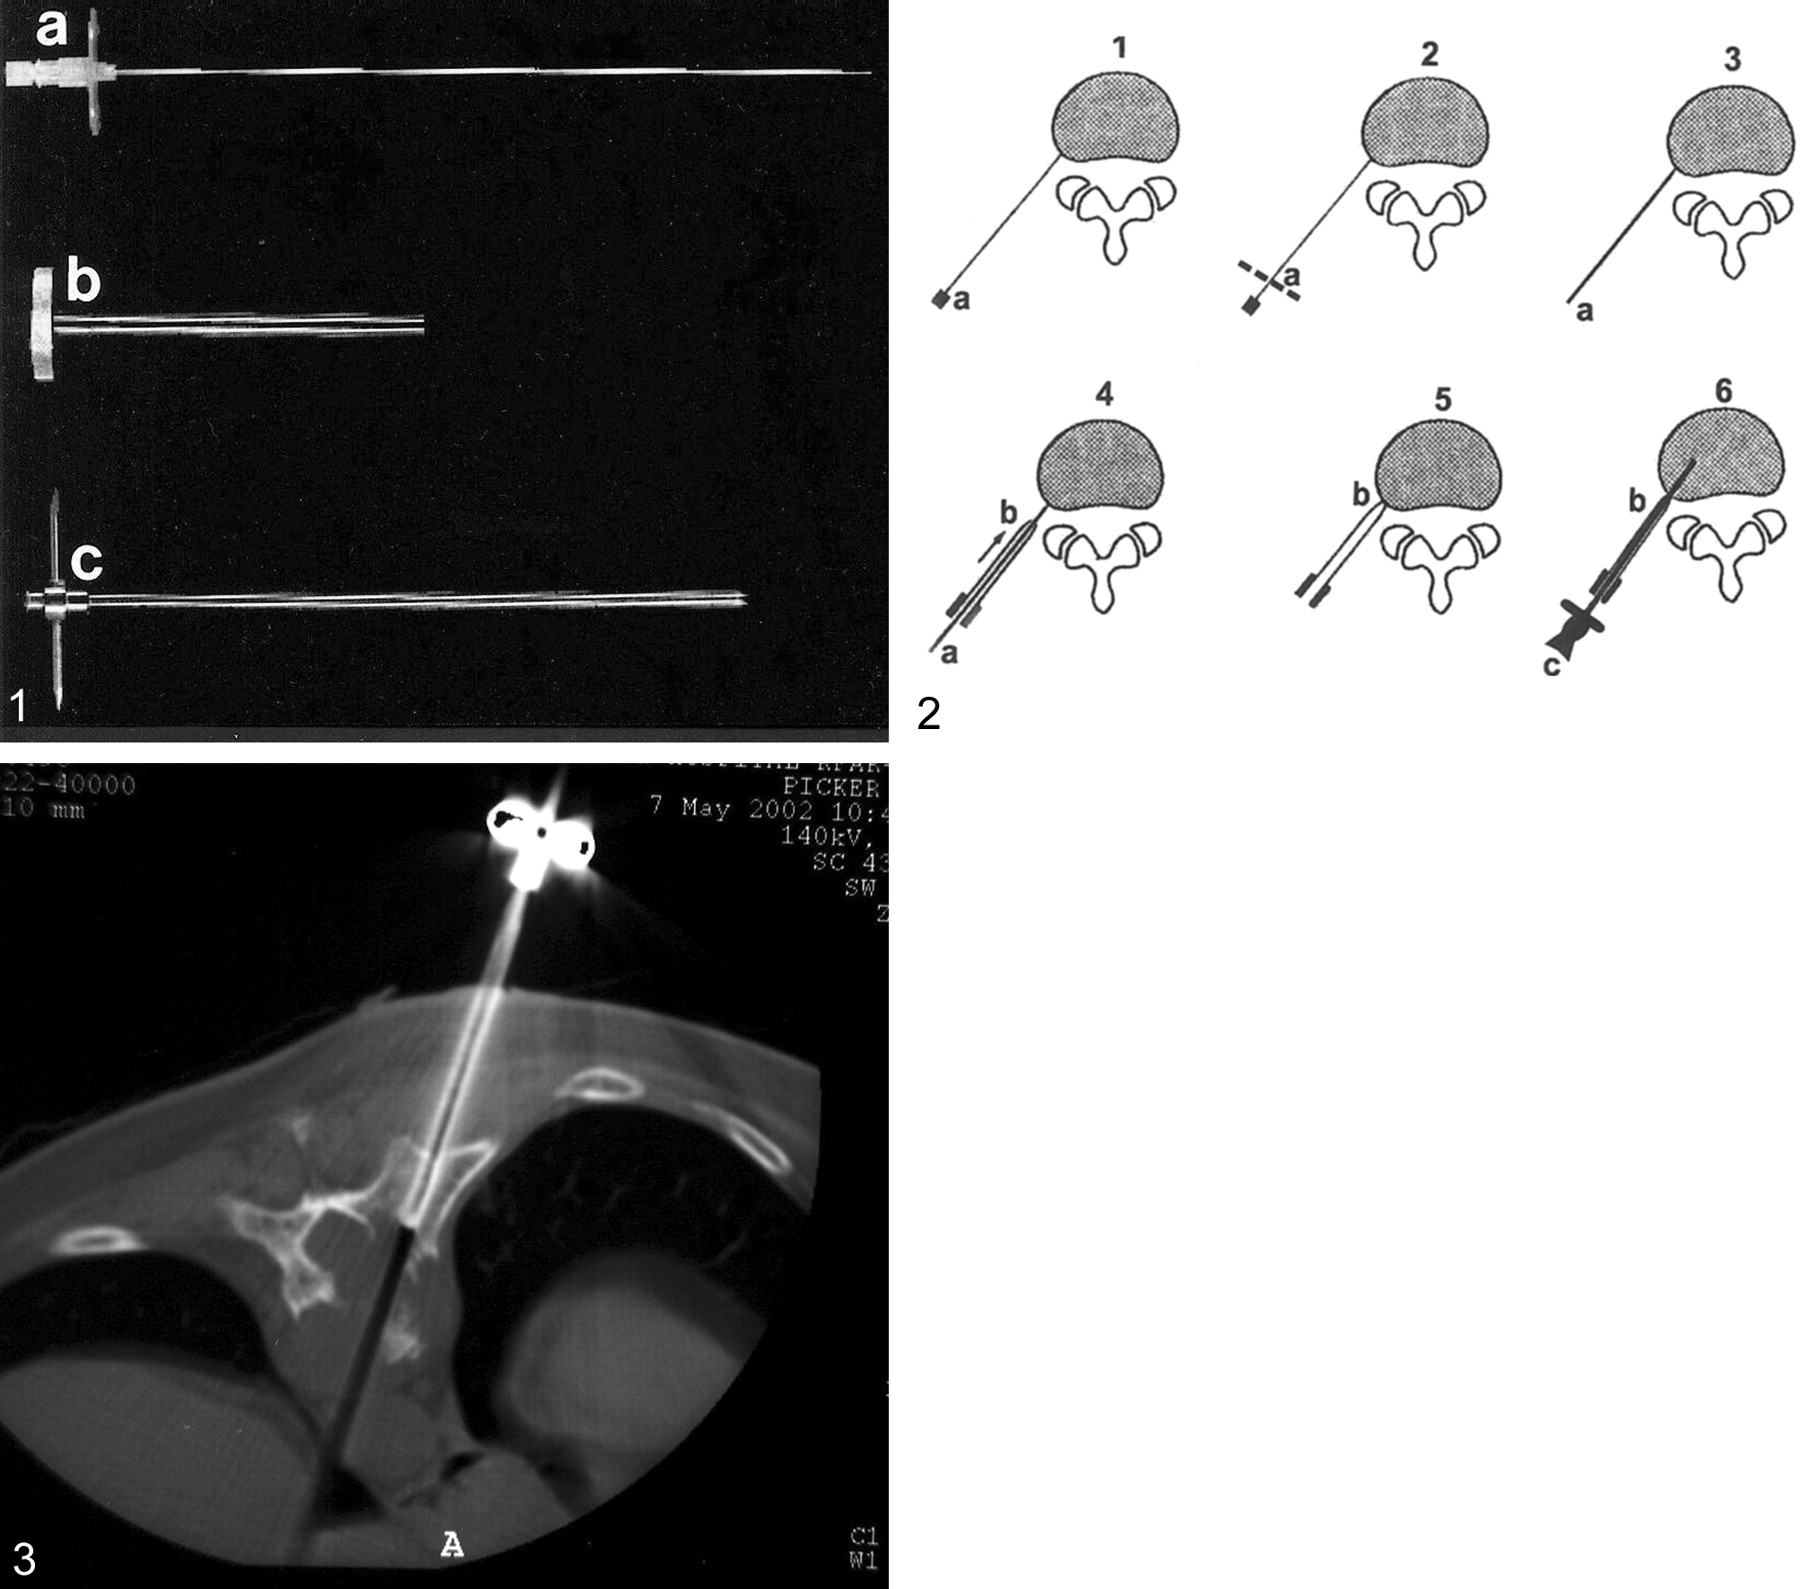

Twelve biopsies were performed with the 8-gauge Jamshidi needle (Manan Medical Products, Inc., Northbrook, IL) and seven with the 8-gauge Waldemar spinal biopsy needle (Link, Hamburg, Germany) (Fig 1). All biopsies were done under CT guidance (Elscint 2400 Elite, Haifa, Israel or Picker International Inc., Cleveland, OH) with the patients in the prone position. Maximum attention was addressed to the patient’s comfort. The lesion was localized, and the point of entry on the skin was marked in accordance with the biopsy technique (4–7). Three approaches were used: posterolateral (n = 2) for the upper lumbar vertebrae; transcostotransversal (n = 6) for the thoracic vertebrae; and transpedicular (n = 11) for the L4-L5 vertebrae and the thoracic spine. At the beginning of the procedure, a local anesthetic (1% Esracaine) was injected subcutaneously with a 25-gauge needle. Thereafter, to anesthetize the tract up to the periosteum, an 18-gauge, 24-cm-long needle (Fig 2) was inserted. When the tip of the needle reached the periosteum, additional Esracaine was injected, and the hub of the needle was cut, transforming it into a guidewire (Fig 2). An external sheath measuring 5.2 mm in diameter was slid over the guidewire by using a rotary motion for deeper penetration, and the wire was removed. The biopsy needle was inserted through the cannula. Before the bone was entered, a scan was obtained to check the location and direction of the needle. The periostium was penetrated by moving the Jamshidi or the Waldemar needle in a clockwise-counterclockwise motion with the sharp pointed stylet. The biopsy needle was then advanced slowly through the cortex to reach the lesion (Fig 3).

Equipment for coaxial vertebral biopsy.

A, An 18-gauge, 24-cm-long anesthetic needle.

B, external sheath cannula 5.2 mm in diameter.

C, Waldemar spine biopsy needle.

Percutaneous vertebral biopsy with the coaxial system. Parts shown in Figure 1 are labeled.

A 35-year-old patient with lytic lesion (plasmocytoma) involving the body of T10. Percutanous trans costal-transverse approach: the tip of the biopsy needle is visible at the margin of the mass.